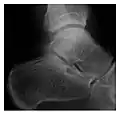

The greater tuberosity of the humerus is also an illustrative location of occult fractures. The osseous injury may follow seizures, glenohumeral dislocation, forced abduction, or direct impaction. They are commonly discovered on MRI in symptomatic patients with suspicion of rotator cuff tear. Coronal images are best suited for detection. They appear as crescentic oblique lines surrounded by a bone marrow edema pattern (Figure 5). The rotator cuff must be inspected since associated ligamentous lesions are common. In the ankle, malleoli and tarsal bones should be checked carefully for any cortical disruptions and radiolucent lines that may reveal a fracture. Awareness of the exact location of the pain will help direct the attention of the interpreter when searching for very subtle signs of fracture (Figure 6).[1]

Figure 6: Subtle anterior talar fracture in a 39-year-old man presenting with ankle pain after a fall. (a) Anteroposterior radiograph shows a subtle oblique radiolucent line through the talus (white arrows). (b) Sagittal CT reformation confirms the presence of an anterior talar fracture with cortical offset (black arrow). Avulsion fractures, which consist of a detached bone fragment resulting from a ligament or tendon pulling away from the bone, may also present with subtle radiographic signs. Tiny osseous fragments near the presumed attachment site of a ligament suggest this diagnosis. Common sites are the lateral tibial plateau (the Segond fracture), the spinal tuberosity of the tibia resulting from anterior cruciate ligament avulsion, and the ischial tuberosity.[1]